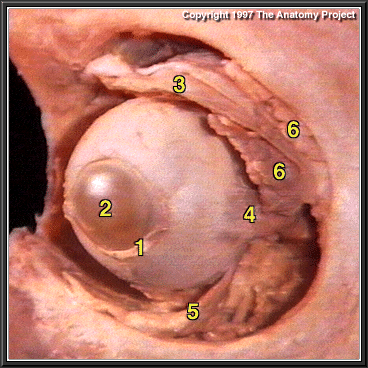

The Eyeball in the Orbit, Oblique Lateral View

Tenon's capsule

Cornea

Levator palpebrae superioris

Lateral rectus

Inferior oblique

Lacrimal gland